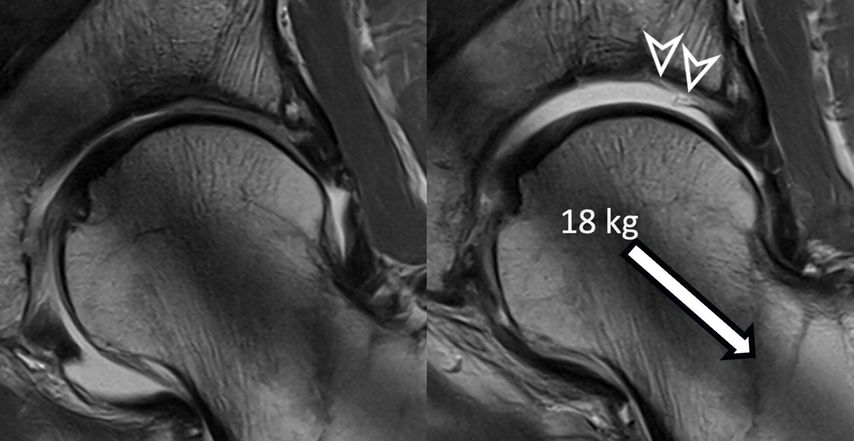

Fig. 2: 3D models of hip cartilage and labrum with color-coded dGEMRIC indices to visualize biochemical cartilage degeneration (red color, black arrowheads) which was confirmed during surgery (white arrowheads).

More recently, we introduced a deep-learning-based approach for automatic segmentation of hip cartilage and labrum using a 3D dGEMRIC sequence (MP2RAGE). The approach allows for automatic and reliable generation of 3D models of hip cartilage and labrum within seconds, and providing both 3D morphologic information of the hip joint as well as color-coded dGEMRIC indices for quantitative analysis of cartilage damage (Fig. 2 & 3).19

Fig. 3: Two patients with cam deformity of the proximal femur. Pelvic X-ray shows in both cases only mild arthritic changes. The morphologic MRI only allows 2D morphologic assessment of damage. The 3D cartilage models allow for a quantitative and 3D assessment of cartilage degeneration. Compared to the patient with good cartilage quality (blue color coding) who underwent impingement surgery the patient below showed too advanced signs of cartilage damage (red color coding) and thus underwent total hip replacement.